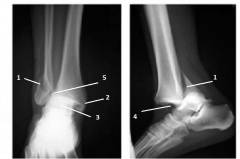

Рис. 5. Схематическое изображение некоторых видов переломов лодыжки:

1 – перелом латеральной лодыжки без смещения (косой и поперечный) – пронация.

2 – перелом латеральной и медиальной лодыжек со смещением, вывих стопы наружу – пронация.

3 – перелом медиальной лодыжки, косой перлом большеберцовой кости без смещения, разрыв межберцового соединения, перелом малоберцовой кости и латеральной лодыжки со смещением, вывих стопы внутрь – супинация.

4 – перелом большеберцовой кости в дистальной части, отрыв латеральной лодыжки, разрыв межберцового соединения, разрыв медиальных связок, подвывих стопы наружу – супинация.

5 – перелом с осколками малоберцовой кости в дистальном отделе, перелом без смещения латеральной лодыжки, косой перелом большеберцовой кости в дистальном отделе, отрыв медиальной лодыжки, разрыв межберцового соединения – супинация.

Рис.7. Рентгенограмма правого голеностопного сустава, прямая и боковая проекция. Закрытый перелом обеих лодыжек со смещением латеральной лодыжки и подвывихом стопы вперед, повреждение всех групп связок голеностопного сустава.(супинационный механизм травмы).

1- линия перелома со смещением латеральной лодыжки,

2- линия перелома без смещения медиальной лодыжки,

3- деформация щели голеностопного сустава, что говорит о повреждении связок латеральной и медиальной групп,

4- смещение голеностопного сустава вперед,

5- субъективный признак повреждения межберцового соединения.

Рис. 8. Прямая рентгенограмма левого голеностопного сустава. Перелом обеих лодыжек с подвывихом стопы наружу, повреждение медиальной группы связок и межберцового соединения.